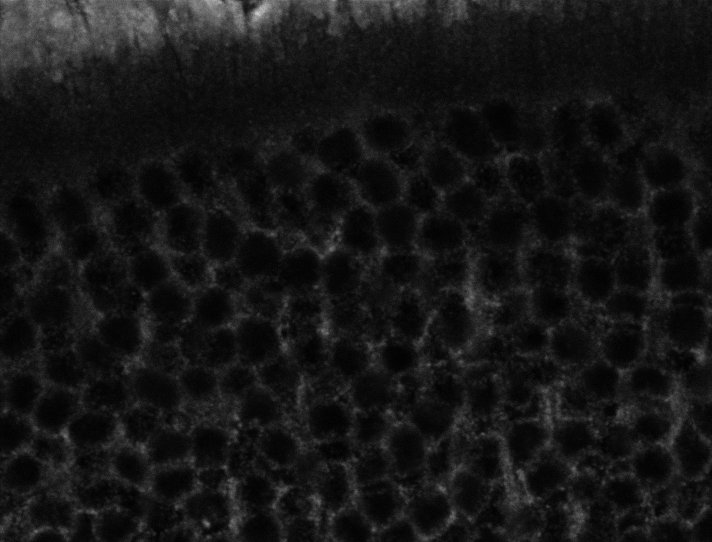

Healthy Choroid